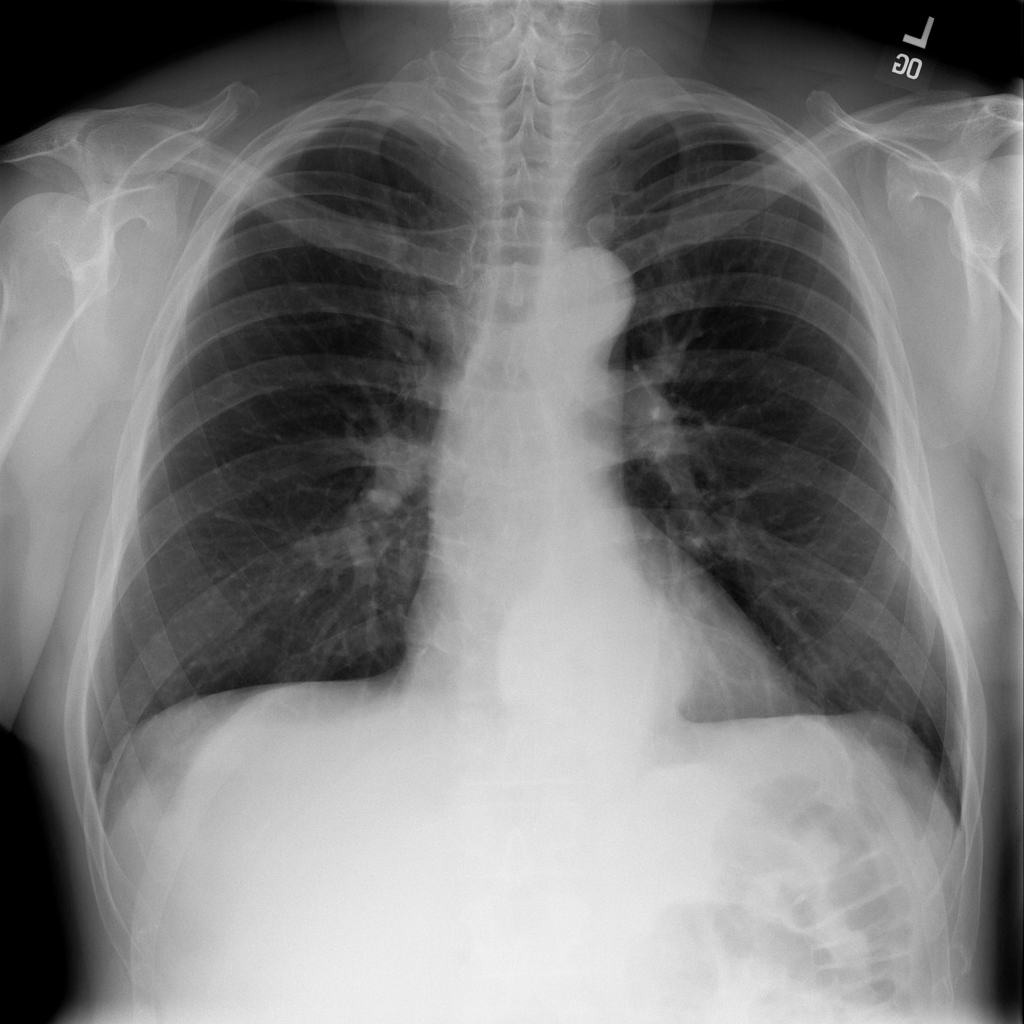

PAT-C048 · IMG-000Hernia

PAT-C048 · IMG-000

PA